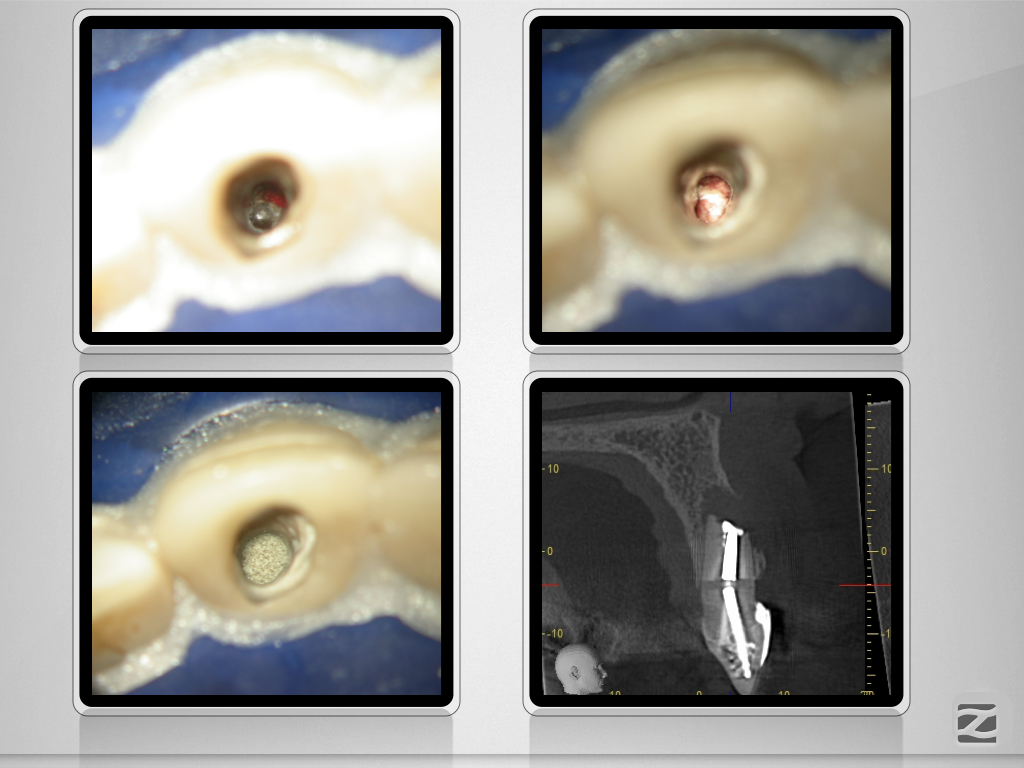

Hürdenlauf – Revision nach Resektion